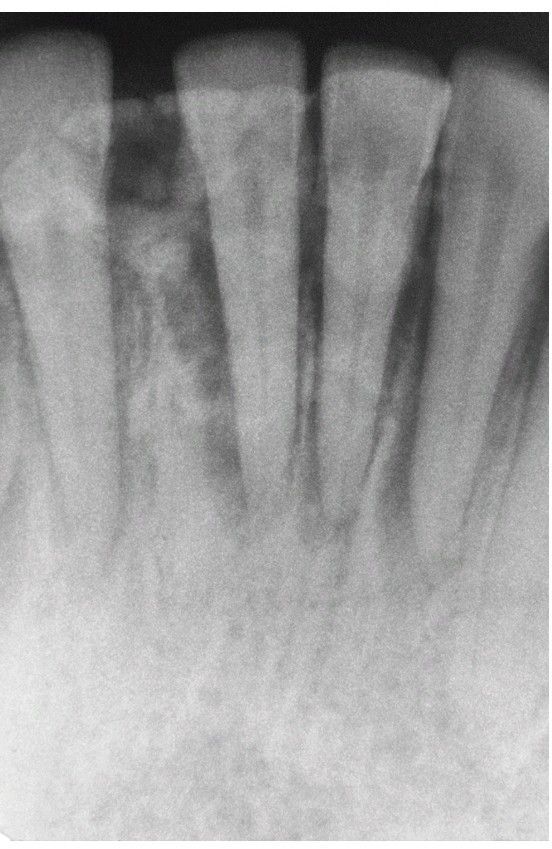

Osteosarcoma

. This 26-year-old woman had a 6-cm painful tumor of the anterior mandible. The periapical radiograph shows widening of the periodontal ligament spaces and a mottled radiopacity superimposed on the teeth.